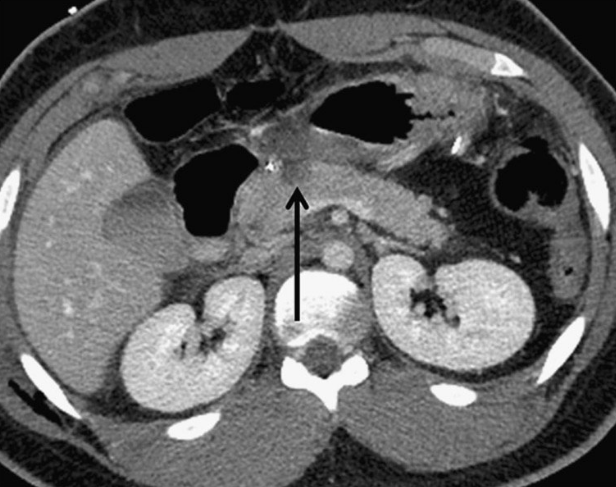

УЗИ диагностика кольцевидной поджелудочной железы: что важно знать